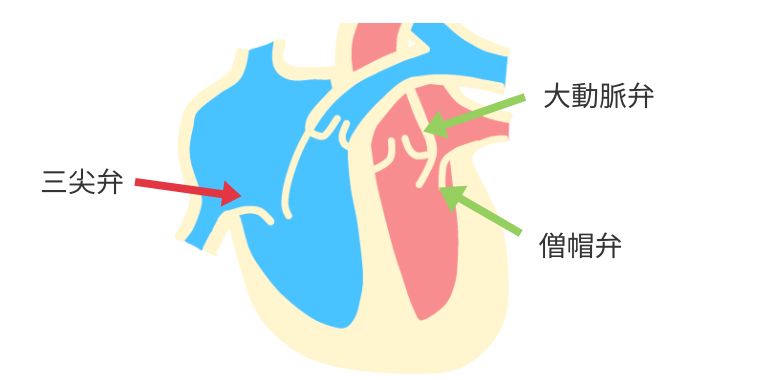

主に大動脈弁、僧帽弁に対する手術です。

三尖弁の手術も同時手術の際に行う場合があります。

僧帽弁は2つの弁と、心臓から弁を引っ張っている腱索というひも状の部分から成り立っています。手術では、切れた腱索の代わりに新しい人工腱索で補強したり、壊れた部分を切ったり縫い合わせたりして修復した後、弁の周りに特殊なリングを縫いつけて形を整えます。弁置換のようにワーファリンの内服は必要でなく、心臓の機能を温存でき長期成績も良好なため、弁形成術を第一選択としています。